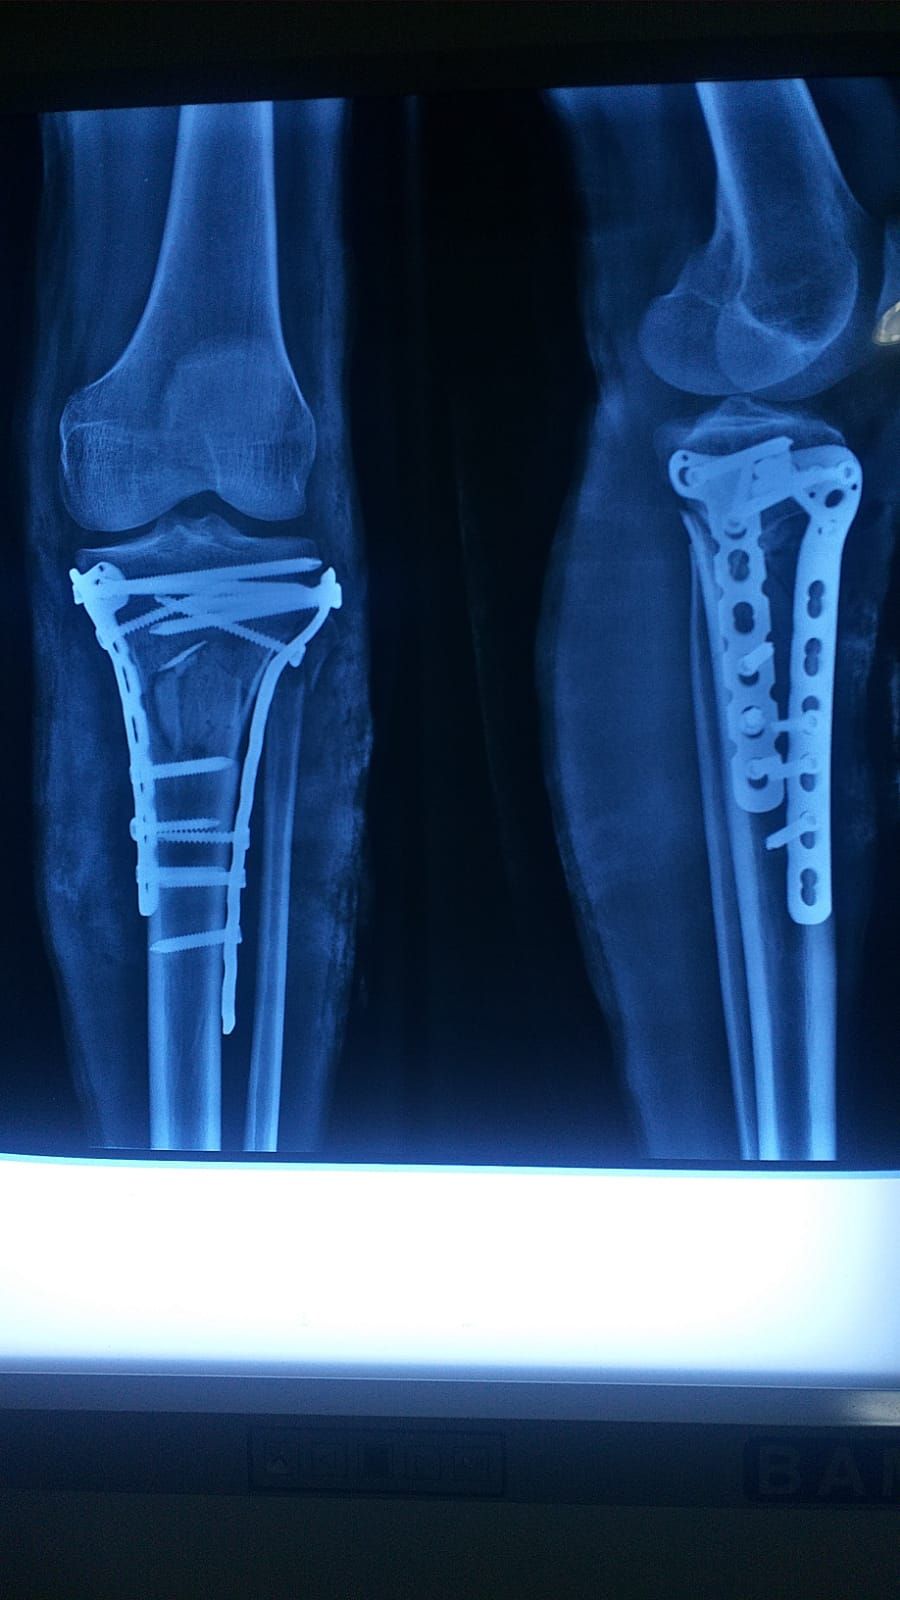

Reparación de fractura de tibia y peroné Sin especificar

Reparación de fractura de la diáfisis tibia o peroné Sin especificar